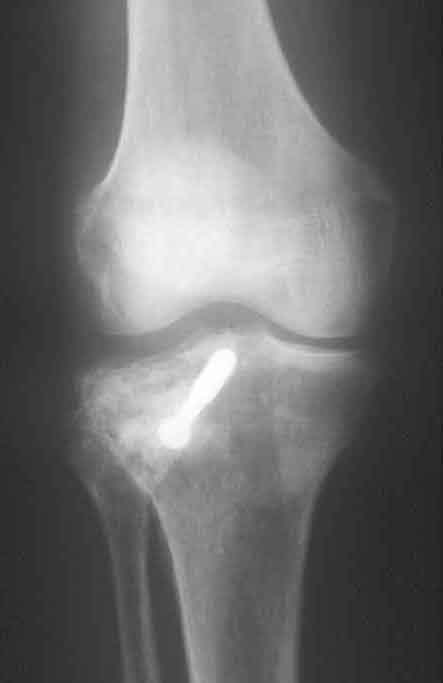

Röntgenbefund nach einem Jahr